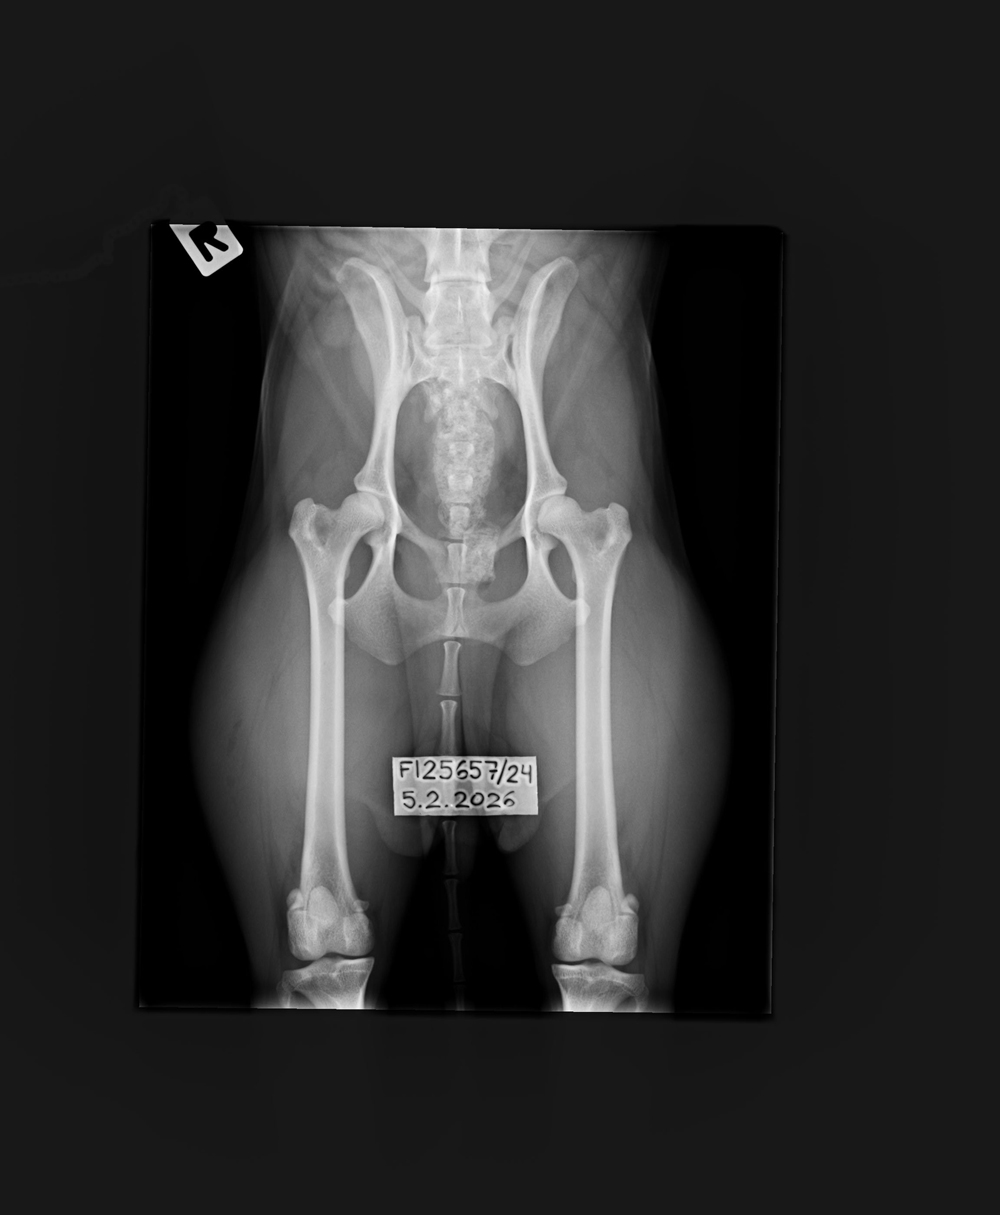

A/A |

0/0 |